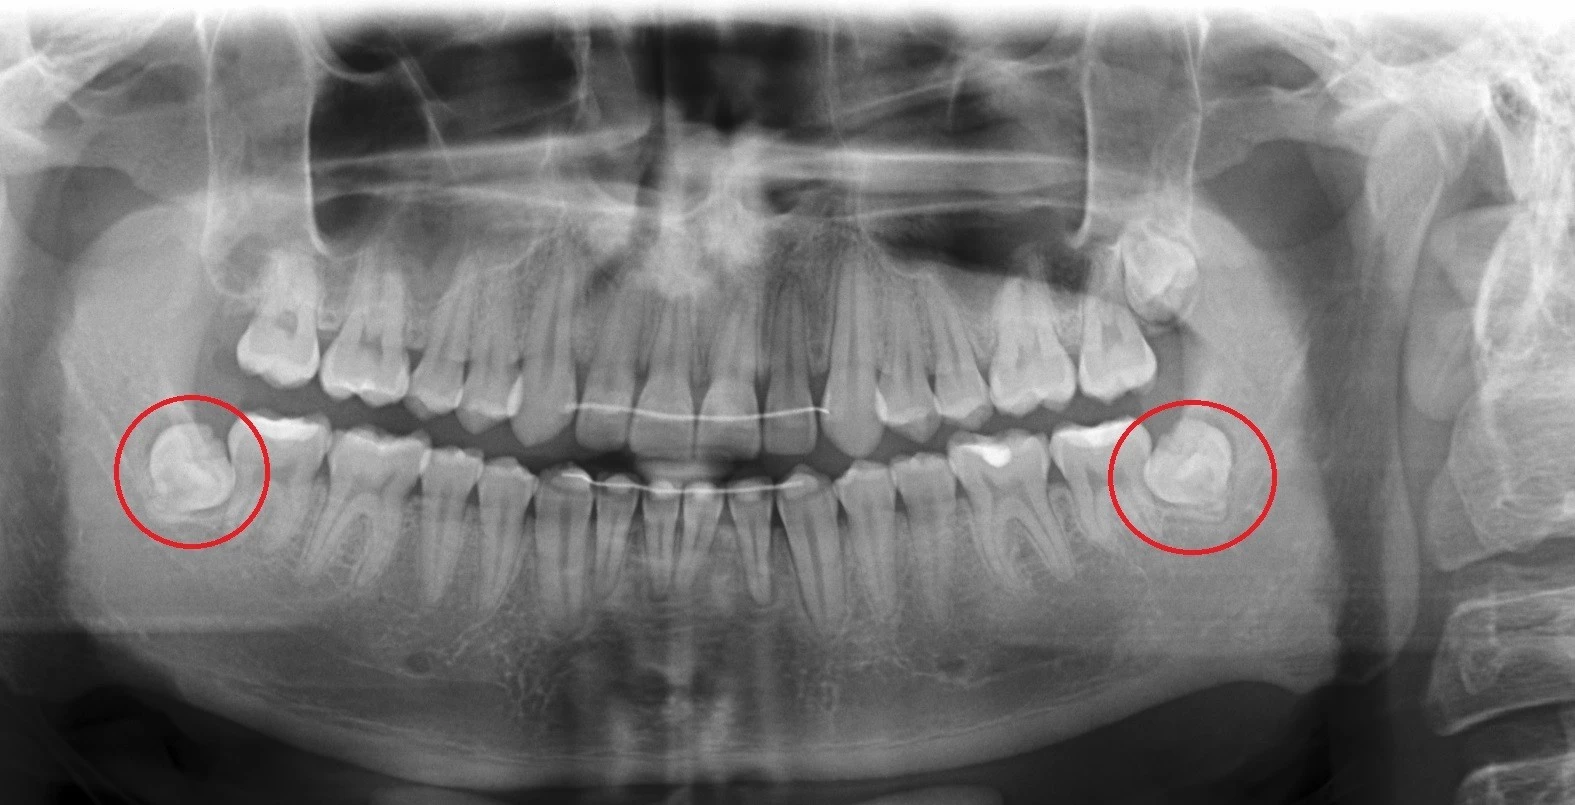

Germektomia jest najczęściej zabiegiem wykonywanym ze wskazań ortodontycznych, polegającym na chirurgicznym usunięciu zawiązka zęba mądrości, czyli "ósemki".

Głównym wskazaniem do germektomii, czyli usunięcia nie w pełni wykształconego zęba, jest zapobieganie stłoczeniom zębów.

Poniżej przedstawiamy germektomię wykonaną u 19-letniego pacjenta przez specjalistę chirurgii stomatologicznej - dr Tomasza Kozioła.